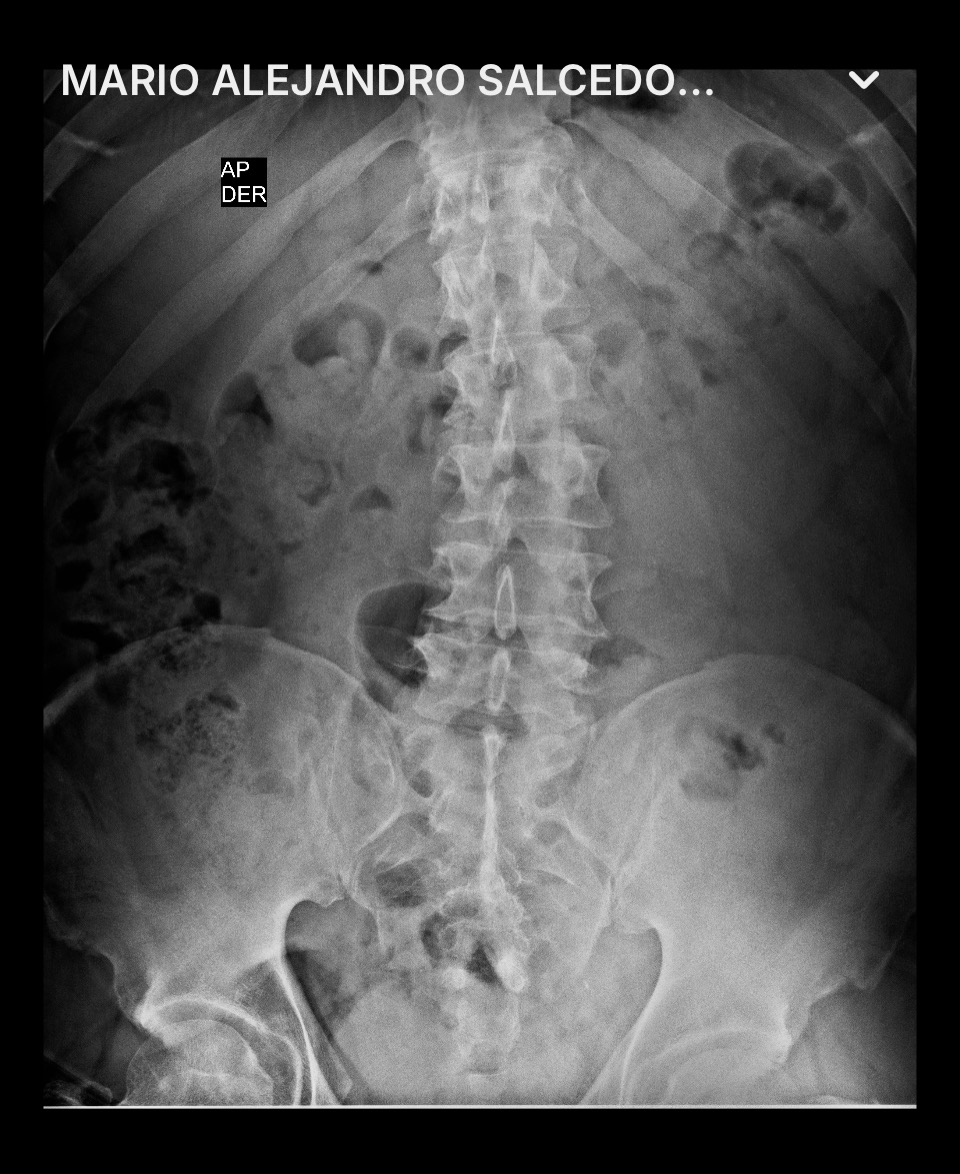

El día martes, 4 de noviembre de 2025, fuimos a ver a un nuevo doctor neurocirujano, que me envió de carácter urgente a realizarme nuevos estudios (RX's y resonancias magnéticas), así como también análisis de sangre y orina.

Este doctor neurocirujano me comentó que ya estaba en una situación de carácter urgente y que tenía que ser intervenido quirúrgicamente, ya que mi médula espinal está comprometida, diciéndome, en otras palabras, que en cualquier momento puedo quedar sentado. Pero que si me opero en este momento, tendría una esperanza para poder recuperarme y disfrutar de una vida normal acompañado de mi esposa e hijas.